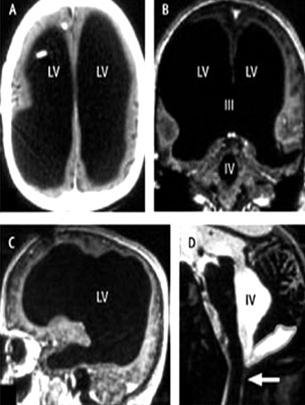

| Các ảnh chụp CT não người bệnh cho thấy dịch tràn đầy các não thất của hộp sọ, và chỉ có một lớp mỏng các mô não dính sát vách hộp sọ - Ảnh: Reuters |

Người đàn ông có gia đình và hai con này nhập viện vì cảm thấy chân trái bị yếu. Sau khi chụp CT và MRI não, các bác sĩ phát hiện não thất của ông nở rộng, trong khi não, tức chất xám và chất trắng, chỉ có một chút và dính sát vách hộp sọ. Feuillet nói: “Những hình ảnh rất không bình thường.... não gần như không có”. Đọc bệnh sử của bệnh nhân, các bác sĩ phát hiện bệnh nhân từ sáu tháng tuổi đã được điều trị tràn dịch não.